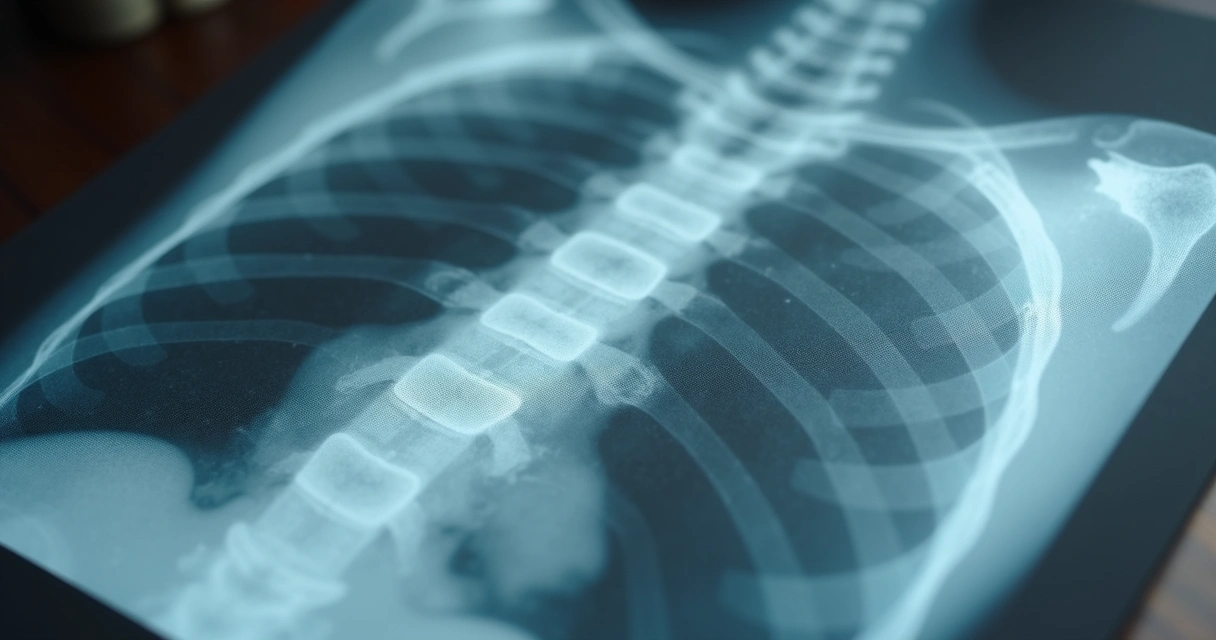

Com a queda dos hormônios femininos, ocorre um risco maior de desenvolver osteoporose, porque os ossos perdem densidade, e doenças cardiovasculares, já que os hormônios protegiam as artérias.

- Osteoporose: A perda óssea acelera após a queda dos níveis de estrogênio, tornando ossos propensos a fraturas.